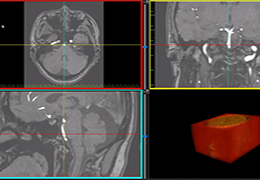

成像智能。

Eclipse 成像智能功能提供强大的处理能力和最佳质量的影像,同时减少质量错误并提高剂量效率。

凭借 AI、专有算法和先进的影像处理能力,提供出色的影像质量和无与伦比的诊断信心。

与标准影像处理相比,智能降噪功能可使客户降低辐射剂量,而不会损失影像质量。这在新生儿和儿科成像中尤其重要,在这种情况下以尽可能低的剂量成像至关重要。

提供相配视图选项,以减少所需的曝光次数,并提供更清晰的感兴趣区域视图。